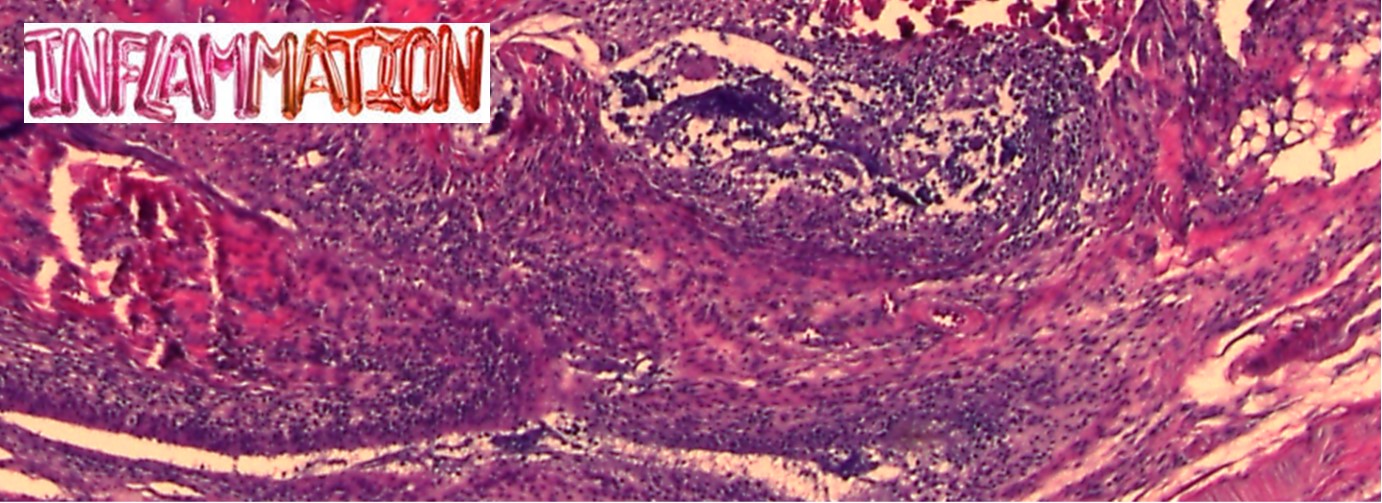

Immunology / Modeling inflammatory diseases and neurodegenerative diseases / Rheumatoid arthritis (RA) / Multiple Sclerosis (MS) / Alzheimer Disease (AD) / preclinical research studies.

- Immunology, focusing on inflammatory autoimmune settings particularly, Multiple sclerosis (MS) and Rheumatoid Arthritis (RA), and their therapeutic targets, the cytokines type I IFNs and TNF respectively.